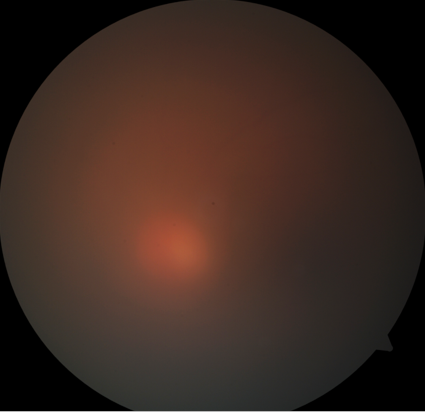

On the 8th day of admission, the patient complained of a sudden painful diminution of vision in the left eye. Ophthalmic examination was done. His best corrected visual acuity was 6/6 in the right eye and hand movements in the left eye. The right eye was within normal limits. Anterior segment examination of the left eye showed lid edema, circumciliary congestion with cells 4+ and flare 3+ with hypopyon. Fundus showed vitreous haze 4+ and vitreous exudates (Figure 3 [Fig. 3]). Retinal details were not clinically visible. B scan ultrasonography showed plenty of low to moderate reflective dot echoes and few membrane echoes in vitreous. The retina was attached throughout. The patient was diagnosed with EE in left eye. The patient underwent vitrectomy with intravitreal vancomycin (1 mg/0.05 ml), ceftazidime (2.25 mg/0.05 ml) and dexamethasone (0.4 mg/0.05 ml) (Figure 4 [Fig. 4]). Vitreous biopsy was sent for microscopy, culture and sensitivity. Vitreous culture showed no growth. Subsequently, intravitreal injections of antibiotics and steroids were repeated three times at an interval of 2 days. Vision improved to 6/9 postoperatively on 2 weeks follow up.

Figure 3: Hazy view of fundus with vitreous exudates